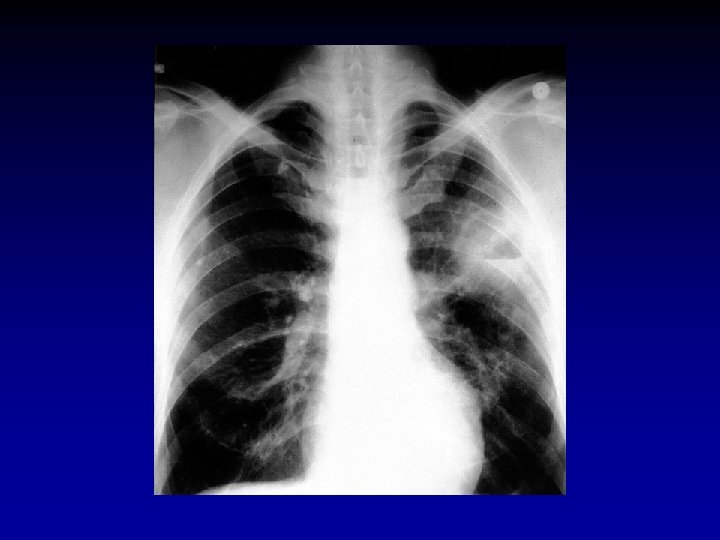

Akciğer Grafisi • Posteroanterior grafi Pnömoninin • Yerini • Komplikasyonlarını • Pnömoniyi taklit eden durumları saptar.

Akciğer Filmi • Pnömoni düşünülen her hastada PA akciğer filmi çekilmelidir • Radyolojik görünümle etyolojik tanıya varmak mümkün değildir • Antibiyotik tedavisine yanıt alınıyorsa bir kontrol filmi yeterlidir • Bazı pnömonili olgularda akciğer filmi normal görünümde olabilir (Pnömoninin ilk 24 saatinde, dehidratasyon, yaşlı, pnömosistis karini, ciddi nötropenik hastalarda)

Akciğer Grafisi • Pnömokok, Klebsiella • Lober tutulum • S. aureus, P. aeruginosa • Bronkopnömonik görünüm • S. aureus • Legionella • Pnömatosel, yeri değişen nodüler infiltrasyonlar, apse • Zaman içinde değişebilir veya baştan itibaren lober